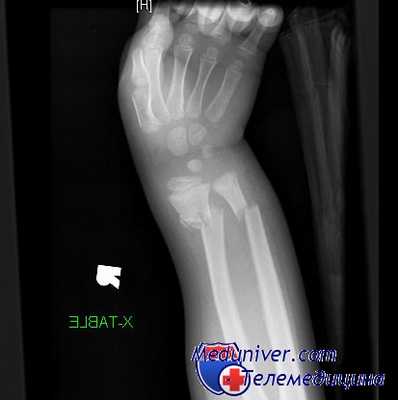

Обследование обычно выявляет боль, припухлость и болезненность при пальпации в области дистального отдела предплечья. В типичных случаях смещенный под углом перелом напоминает вилку, как показано на рисунке. Следует подчеркнуть важность документирования неврологического состояния с особым акцентом на срединный нерв. Боль в локтевом суставе может указывать на вывих или подвывих проксимального лучелоктевого сочленения.

Деформация по типу вилки, описанная при переломах дистального отдела лучевой кости Коллиса

Диагноз выставляется врачом-травматологом на основании анамнестических данных, жалоб, информации, полученной в ходе объективного осмотра, результатов аппаратных исследований. Основным способом визуализации является рентгенография лучезапястного сустава в двух или трех проекциях. На снимках просматривается линия перелома. Периферический отломок смещен в соответствующем направлении.